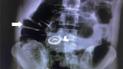

Во Франции медики в прямой кишке мужчины обнаружили 20-сантиметровый артиллерийский снаряд времен Первой мировой войны. Из-за этого больницу, где спасали пациента, пришлось эвакуировать.

«Он находился в состоянии сильного дискомфорта, вставив большой предмет в прямую кишку. Была проведена экстренная операция, и оказалось, что этот предмет — артиллерийский снаряд времен Первой мировой войны. Что хуже, он не взорвался, поэтому пришлось вызывать саперов для обезвреживания снаряда, а пожарная бригада была в готовности», — говорится в материале.

37-миллиметровый латунный и медный снаряд имел длину 20 см и использовался Имперской немецкой армией в конце Первой мировой войны.